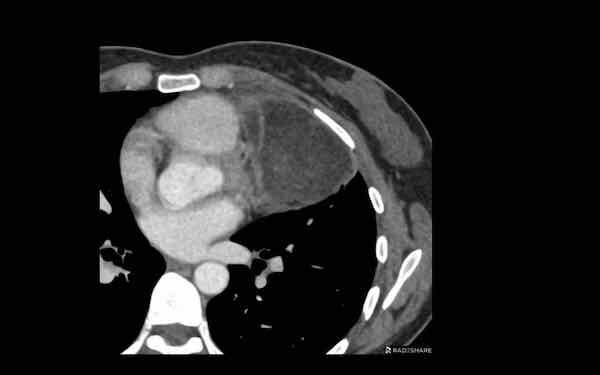

Các hình ảnh này của một bệnh nhân nam 68 tuổi, vừa trải qua phẫu thuật bắc cầu động mạch vành.

Bệnh nhân than phiền khó thở.

Nồng độ D-dimer cao và CT được thực hiện để tìm kiếm thuyên tắc phổi.

Hình ảnh

Có một khối trong trung thất trước mạch máu.

Tỷ trọng là 44